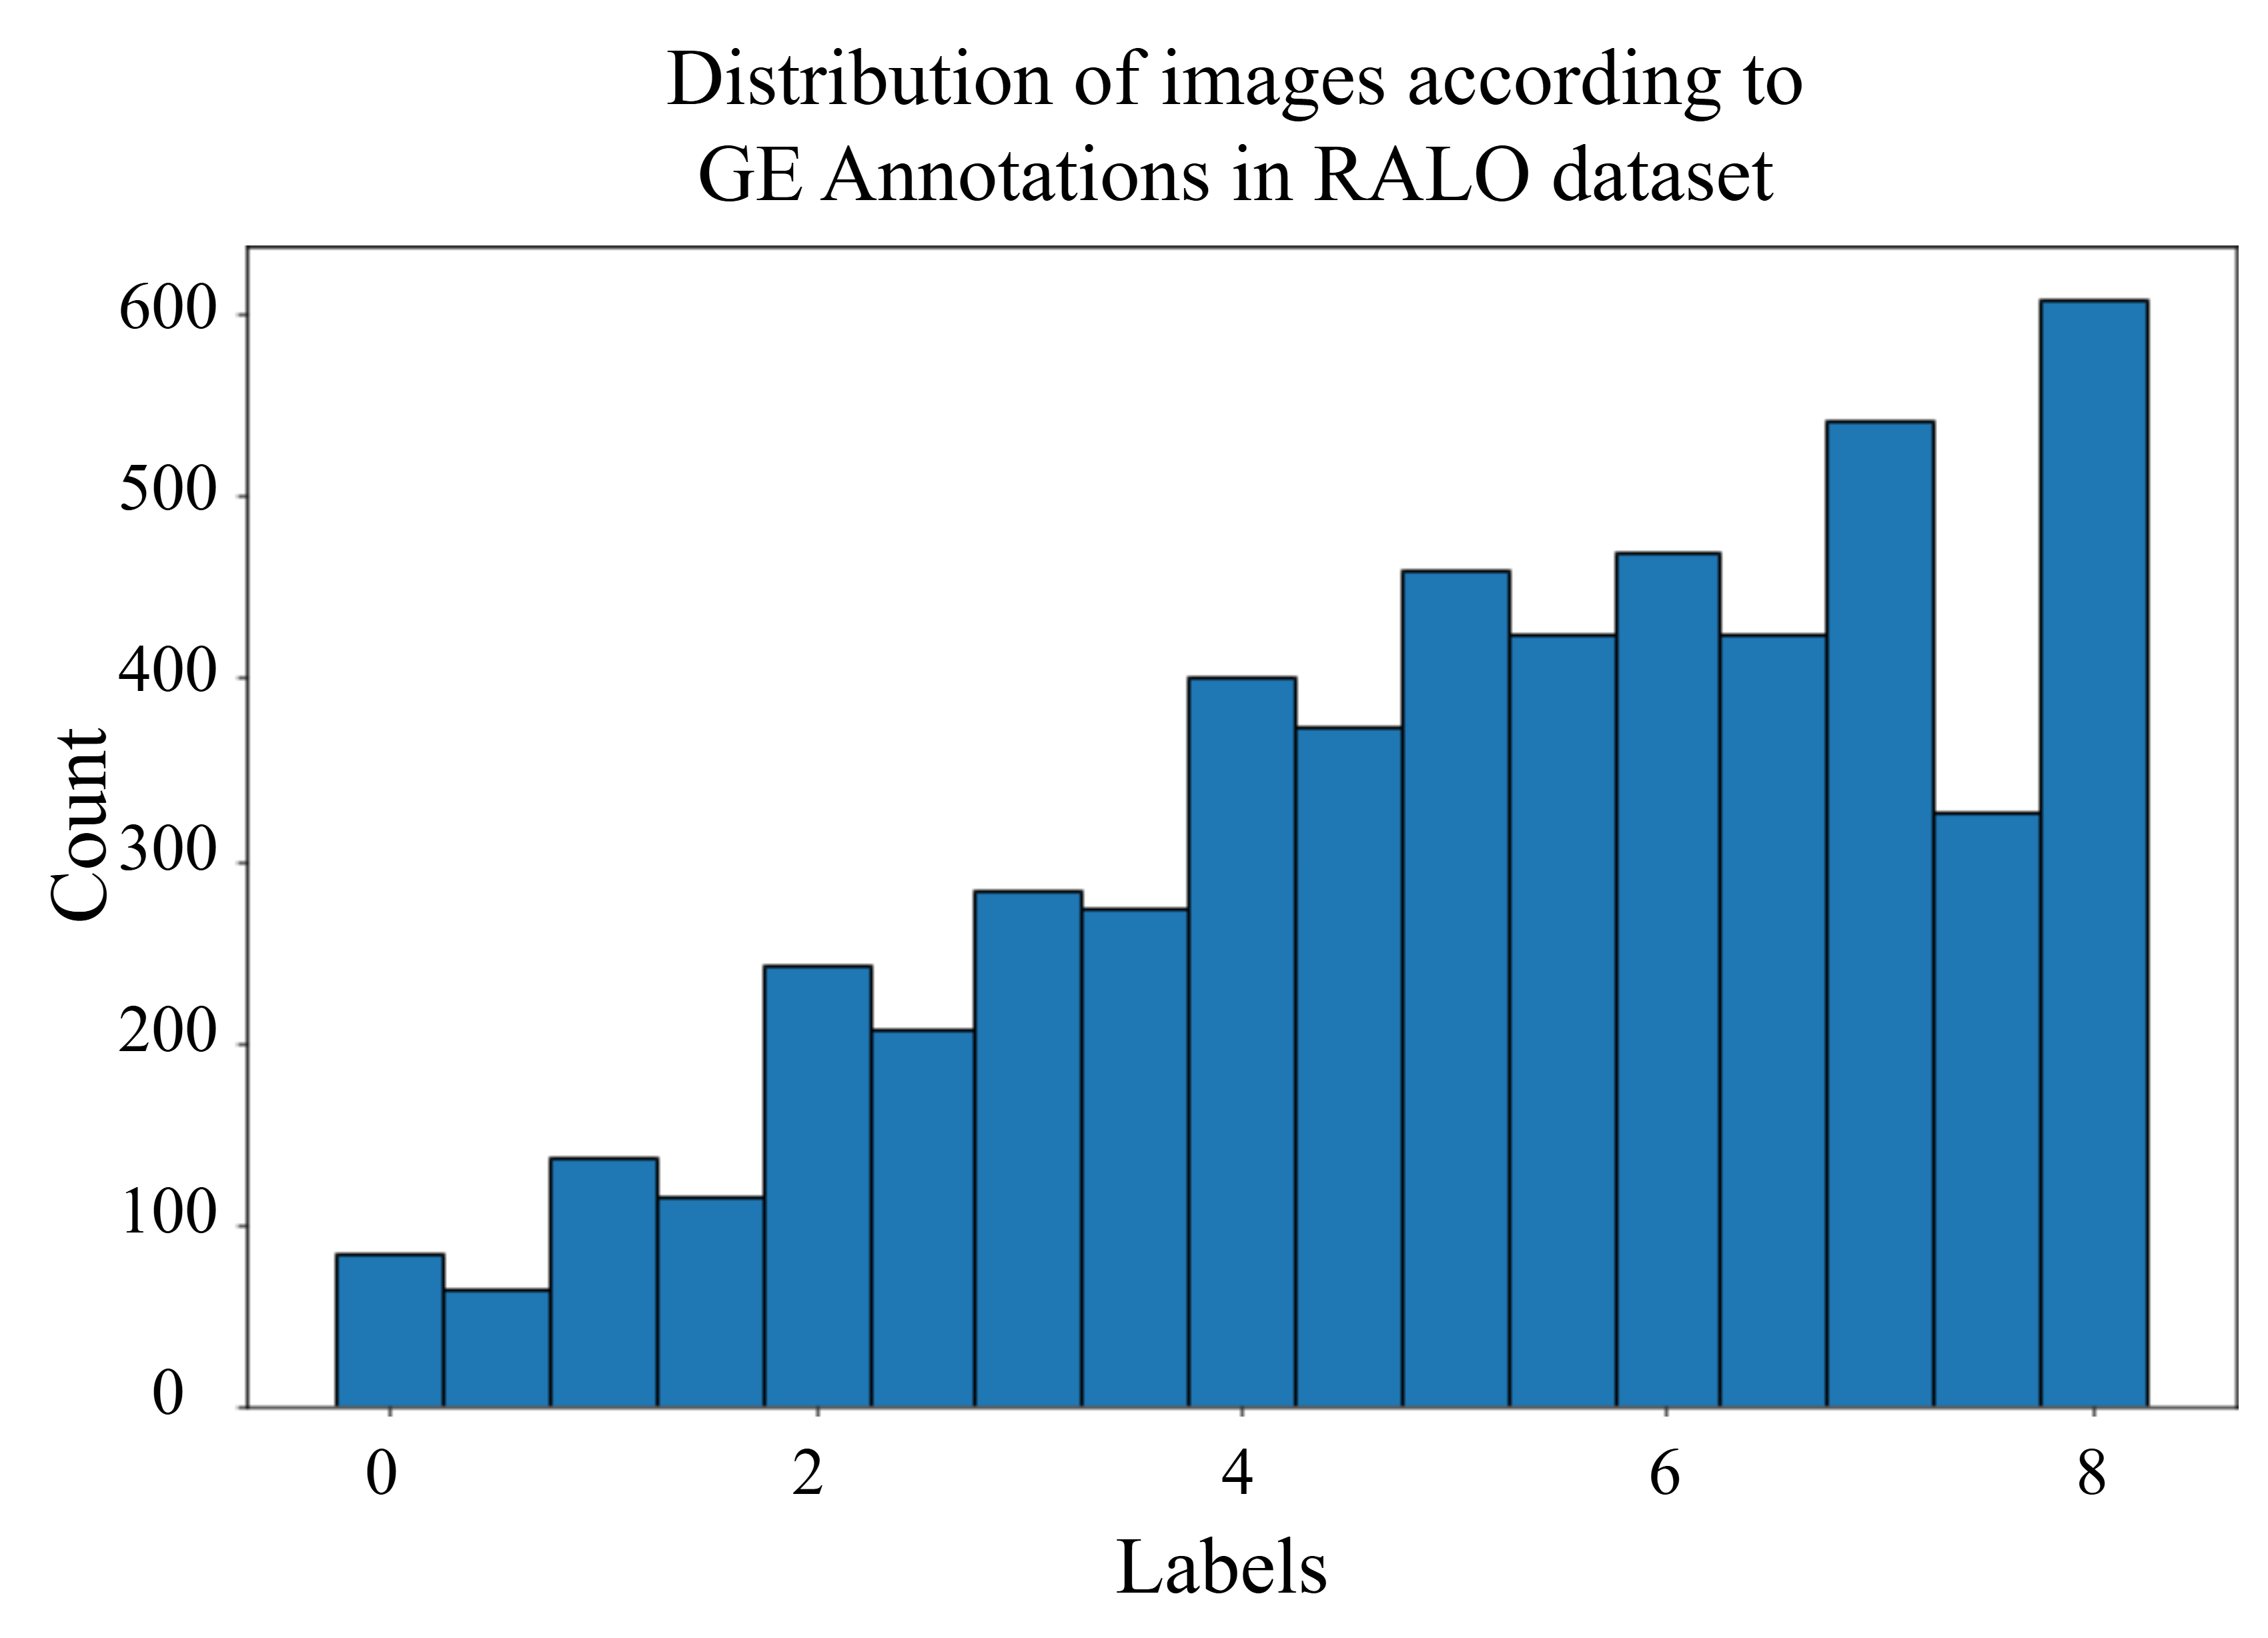

The primary goal of this research is to evaluate the effectiveness of deep learning models in determining the severity of lung diseases. To accomplish this, we utilized the Radiographic Assessment of Lung Opacity Score (RALO) dataset, which consists of 2,373 chest X-ray images [16]. These images were carefully evaluated and scored by two expert radiologists from Stony Brook Medicine to create a detailed COVID-19 dataset for research purposes. The dataset is divided into a training set of 1,878 images and a test set of 495 images. In this study, radiological grading focuses on two key criteria: Geographic Extent (GE) and Lung Opacity (LO). GE refers to the spread of lung involvement by ground-glass opacity or consolidation, with separate scores for the right and left lungs. The GE score ranges from 0 (no consolidation) to 4 (maximum consolidation), and the overall GE score is the sum of the left and right lung scores. LO is assessed independently for each lung, with scores ranging from 0 (no opacity) to 4 (total whiteout), reflecting varying degrees of lung opacity. The total LO score, which ranges from 0 to 8 points, is calculated by summing the scores of both lungs. The final ground-truth scores are averages of the two radiologists’ evaluations, and they are represented in the set [53]. An offline combined lung and score replacement is applied to the training set as done in a previous work [42]. The resultant dataset is distributed as shown in Figure 4.

In this context, the threshold values used for applying Conditional TransMix are chosen according to the initial distribution of the labels across the dataset. Figure 4 illustrates the distribution of GE scores across the dataset, revealing that images with a score greater than 4 are more prevalent than those with a score of 4 or less. This imbalance suggests a natural division within the data, prompting us to use a score of 4 as a threshold. By setting this threshold, we effectively distinguish between cases with higher and lower severity, allowing for targeting the less frequent data with the proposed augmentation method. Similarly, for the LO scores, images with scores below 2 and above 6 are less frequent compared to those within the mid-range scores. This uneven distribution highlights the scarcity of cases with either very low or very high severity, which could pose challenges for the model’s training and evaluation. Understanding this distribution is crucial for applying the augmentation to the scarce data to ensure balanced representation and accurate predictions across all severity levels.